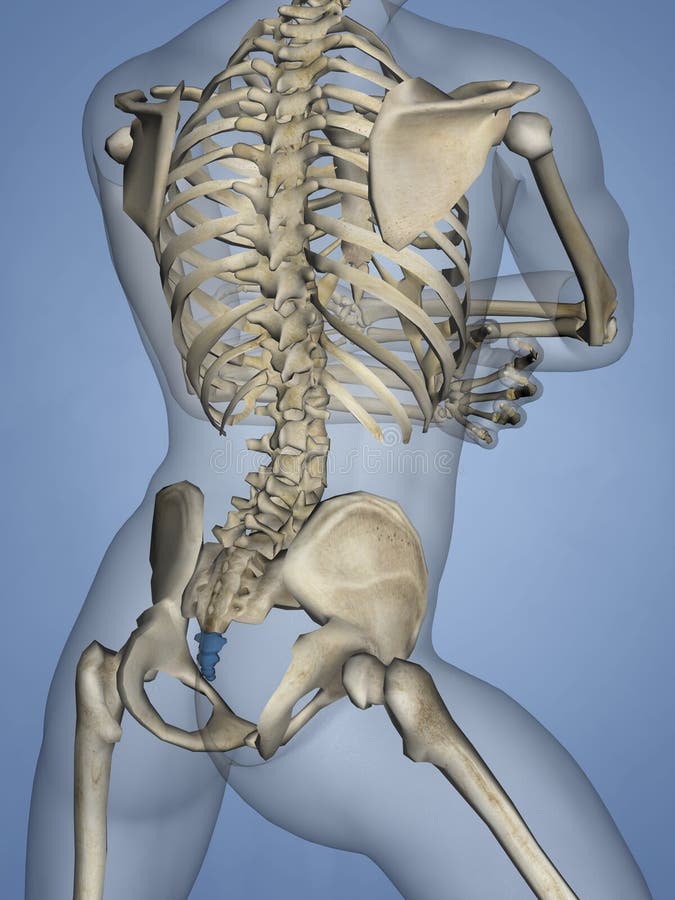

Рентгеновские снимки крестцово-копчикового отдела позвоночника